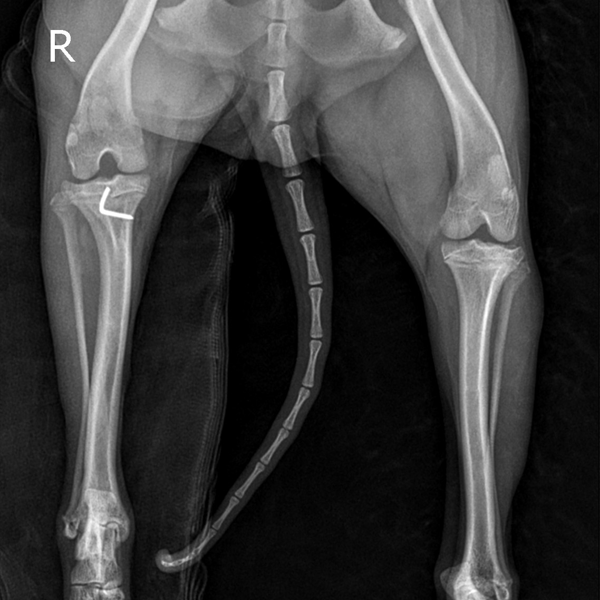

수술 전

(Before)

수술 후

(Afrer)